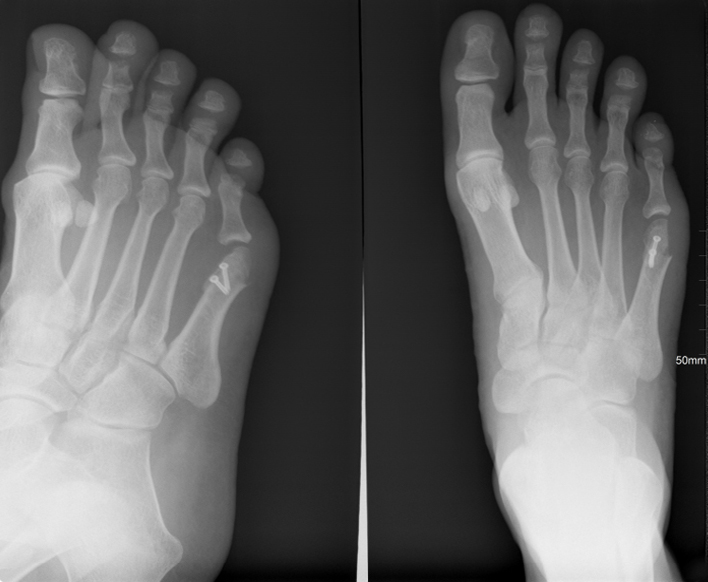

Pre op AP view hammer toes 2-5

Post op oblique and AP views hammer toes 2-5